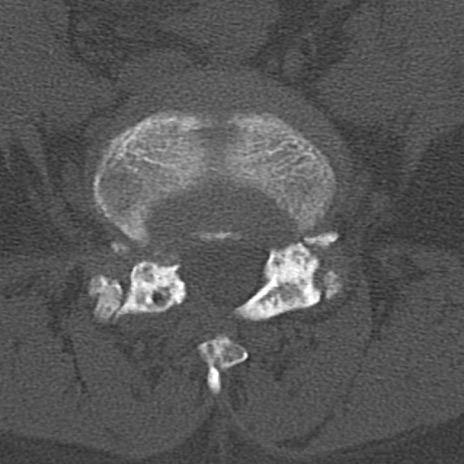

腰椎CT

横断像と矢状断像